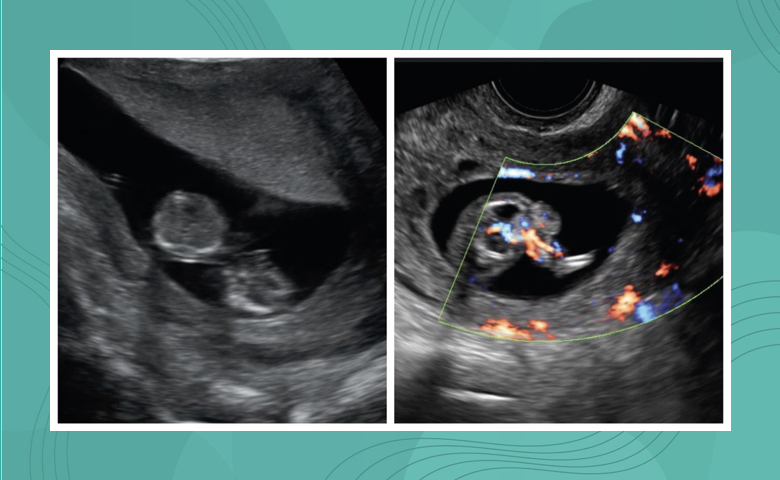

Una primigesta de 41 años con gestación doble monocoriónica biamniótica, con diagnóstico de secuencia perfusión gemelar arterial reversa (TRAP, por sus siglas en inglés) y mal pronóstico perinatal fue intervenida mediante terapia laser intrafetal a las 18 semanas de gestación. Se complicó con rotura prematura de membranas que fue manejada en forma expectante hasta las 33 semanas 3 días, cuando se realizó cesárea electiva sin complicaciones. Se obtuvo un recién nacido vivo sano de 2,255 g que fue dado de alta hospitalaria el día 15 de nacido, sin complicaciones.

Comunicamos el primer caso de terapia laser intrafetal realizado en nuestro país y resaltamos su eficacia, sencillez, bajo costo y abordaje ambulatorio en casos de secuencia TRAP.